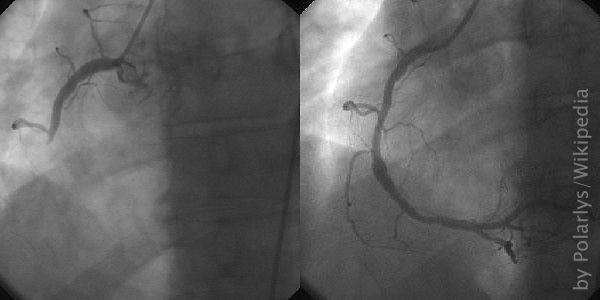

Herzensangelegenheit Gefaesse Dd

Tauchen – eine Herzensangelegenheit